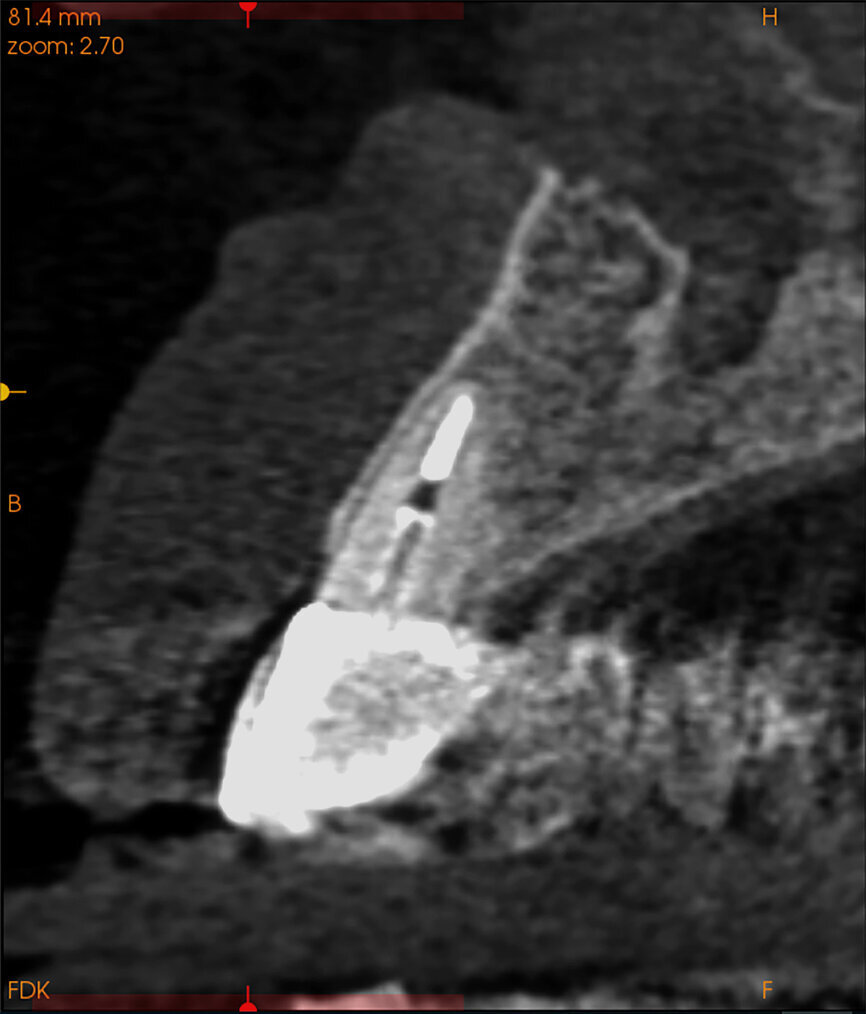

Fig. 2: The trajectory of the root

in relation to the alveolus can be visualised with a cross-sectional image.

The CBCT cross-sectional image revealed a favourable pre-op condition for a PET procedure.

One indication for PET is when a patient presents with a horizontally fractured clinical crown (Fig. 1). While a 2D radiograph will reveal the extent of the horizontal fracture, length of the remaining root and approximation of the bone apical to the root, there is not enough information to plan for a PET procedure. A CBCT scan is recommended in order to fully appreciate the root position within the alveolus and the potential difference between the trajectory of the bone and the trajectory of the root as can be visualised with a cross-sectional image (Fig. 2). Utilising interactive treatment planning software makes it possible to plan the initial drill path to accurately section the root to its apex (Fig. 3a). This can be accomplished by creating a custom implant design to match the diameter of the initial drill with an abutment projection in order to fully appreciate the trajectory through the clinical crown (Blue Sky Plan, Blue Sky Bio). It is important to visualise the root fragment that will remain in order to properly simulate the position of the implant in the alveolus (Fig. 3b). The apical portion of the implant can be positioned to gain stability in host bone using the Triangle of Bone. It is important to note that a cross-sectional slice may only be 0.125 mm in thickness based on the CBCT acquisition, and therefore all images in all views must be visualised to confirm the plan. Utilising 3D segmentation (separating objects by density values), it is possible to define each root and further assess the simulated position of the implant with a sagittal cut through the 3D reconstructed volume (Fig. 4).

A 62-year-old male patient presented with a hopeless prognosis for a post fracture in the left central incisor requiring extraction (Figs. 12a & b). The preoperative periapical radiograph revealed an existing implant supporting a metal–ceramic restoration for the adjacent region #11 (Fig. 13). The CBCT (CS 9600, Carestream Dental) cross-sectional image revealed a favourable preoperative condition relating to the trajectory of the endodontically treated root to the alveolus for a PET procedure (Fig. 14a). Using the native Carestream 3D Imaging software, a simulated implant and abutment projection was positioned within the available bone to avoid the root fragment (Fig. 14b).